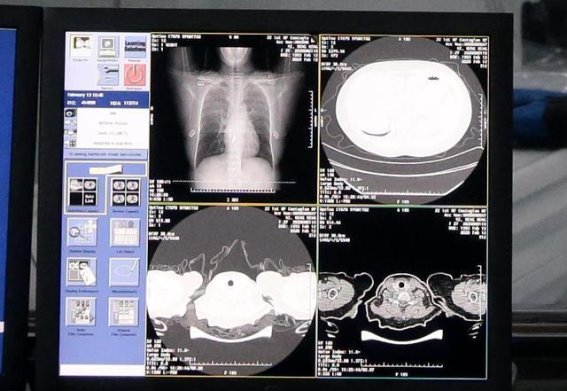

喉咙的不适和轻微咳嗽虽然常见,但很难仅凭症状确诊肺炎。在临床诊疗中,影像学检查,如胸部X光或CT扫描,是早期发现肺炎的重要手段。影像学可以直观地显示肺部是否存在炎症或感染,为医生提供明确依据,判断是否需要进一步治疗。研究表明,早期通过胸部CT发现肺部炎症,能够显著提高治疗效果。尤其是在症状不典型或较轻的患者中,影像学检查能够及时发现病变,防止病情恶化。

喉咙的不适可能只是轻微的信号,但它传递的信息不容忽视。持续的喉咙痛、干涩或轻微咳嗽,如果随着时间推移未见缓解,应立即重视肺炎的可能性。及时就医、进行影像学检查和早期治疗,能够有效防止病情加重,减少并发症的风险。与此保持健康生活方式、减少空气污染暴露、增强免疫力,是降低肺炎风险的重要措施。关注喉咙的微小变化,正是保护呼吸系统健康的重要前提。

肺炎的第一个信号往往隐藏在喉咙的微小变化中,容易被忽略。通过关注喉咙的不适、重视空气环境和生活习惯、及时进行影像学检查和增强免疫力,可以有效防控肺炎的发生与发展。这提醒我们,身体的细微警告不可轻视,早期发现、及时干预,是保障呼吸健康、维护生活质量的关键所在。